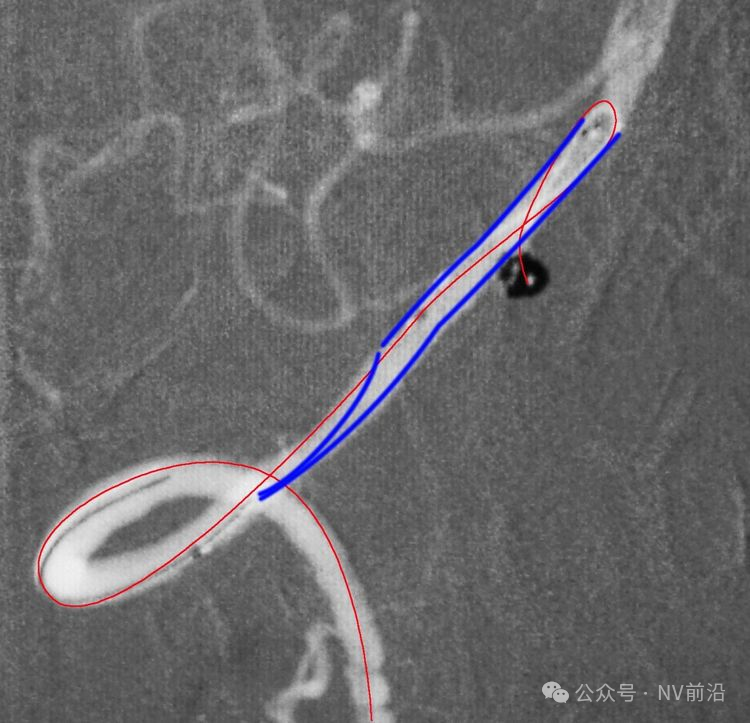

将微导管在虹吸弯处成襻,越过瘤颈,管头折返钩入瘤腔,即所谓回马枪技术。

Solitaire 4×15支架(绿线)跨瘤颈半释放,压住微导管(红线)。